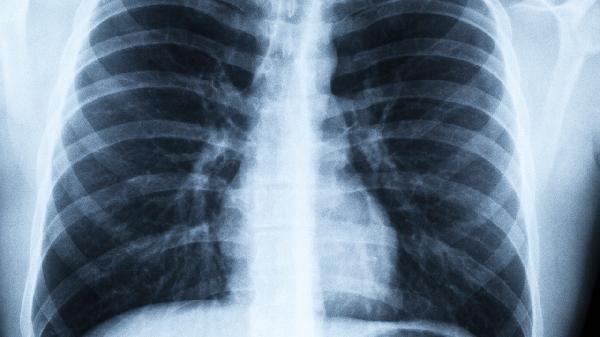

一、30年烟龄的肺经历了什么

1、支气管变身"油烟机"

每天20支烟持续吸入,支气管绒毛会像被油炸过般板结。这些本该过滤灰尘的"小刷子"逐渐失去功能,让致癌物长驱直入。

2、肺泡变成"破气球"

健康肺像饱满的葡萄串,而老烟枪的肺泡会粘连成大小不一的空泡。北京胸科医院病理标本显示,吸烟者的肺泡扩张程度是常人的3倍。

3、免疫系统"罢工"

烟雾中的氰化物会麻痹肺部巨噬细胞。这些"清道夫"本应吞噬癌细胞,却会在尼古丁中逐渐失去战斗力。